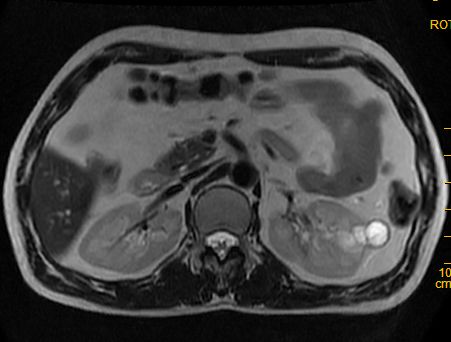

标题: MRI2883:左肾占位性病灶,请大家来会诊!

左肾占位性病灶,请大家来会诊!

考虑多发囊肿融合

肾癌

多囊性肾瘤

考虑 1囊性肾癌 2多囊性肾瘤。

考虑左肾囊性肾癌,多囊性肾瘤待排。

考虑左肾囊性肾癌,多囊性肾瘤待排。建议增强。

左肾癌囊变。

左肾复杂性外生囊肿,错构瘤待排。